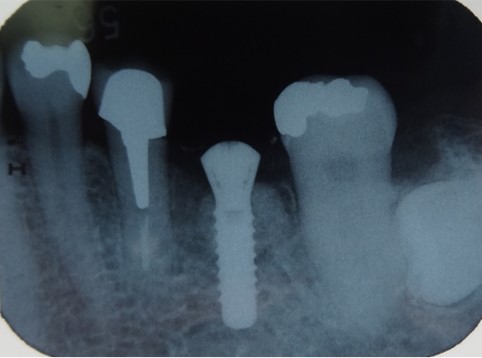

骨の形によっては、インプラントを埋入すると一部が口の中に露出することがあります。露出した部分をそのままにすると細菌が集まり、骨が吸収する原因となるので、露出した部分には人工骨などで覆い骨を作ります。先に人工骨で骨を作り、しっかりと骨ができた段階でインプラントを埋入することもあります。

インプラントを埋入すると部分的に露出したので人工骨で覆いました。